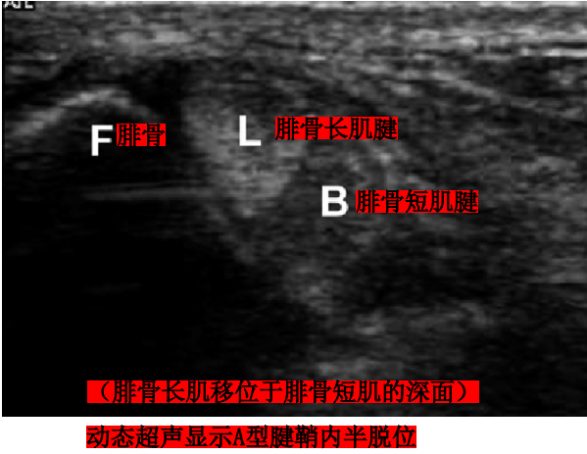

Raikin等学者提出将腓骨沟内腱鞘内半脱位不伴有腓骨上支持带损伤划为腓骨脱位的亚系。这些腱鞘内半脱位共有两型:

A型:腓骨肌腱无撕裂,肌腱暂时换位;

超声:在踝关节背伸、外翻动态活动过程中,可以实现实时动态观察腓骨肌腱。